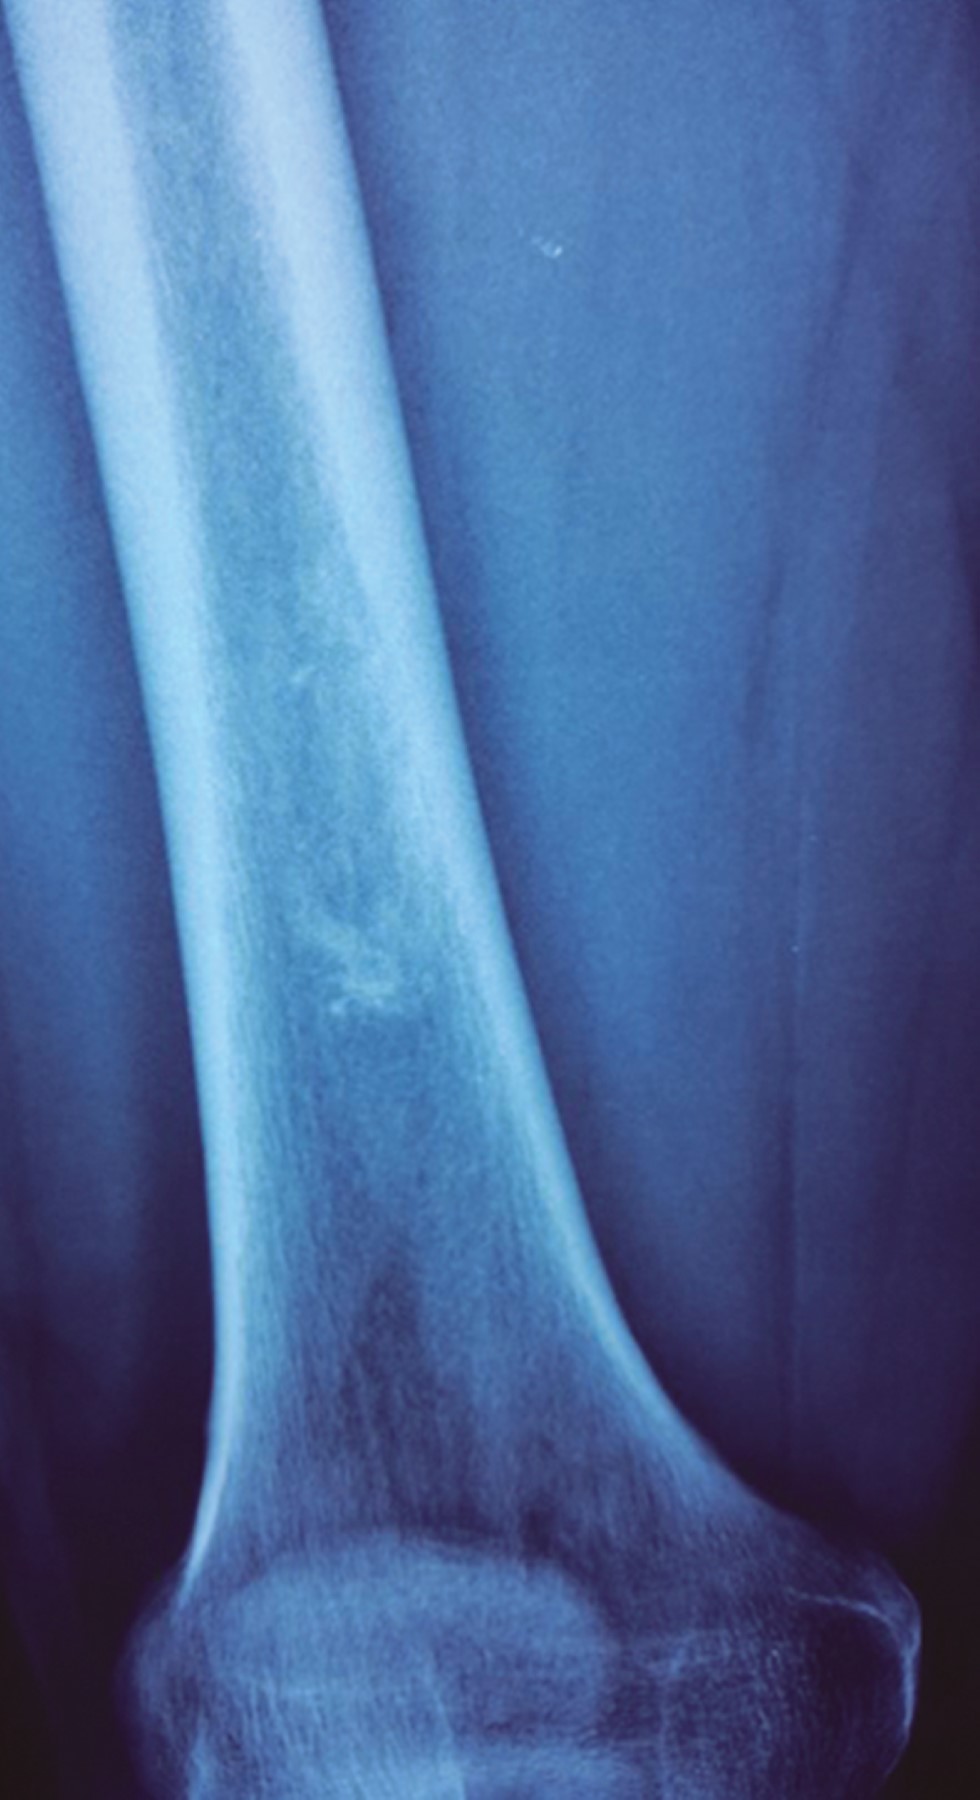

Femoral bone reconstruction after tumor resection, a case report and literature review

Chondrosarcoma are malignant tumors constituted by cartilaginous tissues, the second most common type after osteosarcoma among musculoskeletal tumors, as a general rule they are not sensitive to chemotherapy nor radiotherapy, therefore the treatment involves wide surgical resection with limb salvage, resulting in a bone defect that needs to be reconstructed. reconstruction options available range from endoprostheses, adjuvants after curettage or biological reconstruction using autograft or allograft. Here is a clinical case report of a male patient with massive femoral bone loss, following the resection of a central chondrosarcoma; the bone reconstruction was performed using segmental bone allograft and autograft in combination with platelet rich plasma (PRP), bone marrow aspirate (BMA) and Gelfoam, the reconstruction was stabilized with osteosynthesis material, specifically a locked compression plate (LCP). Strict follow-up was conducted until graft consolidation and integration, which occurred 12 months after the latest surgery. This technique is based on adherence to the principles of the recently introduced "diamond concept", which provides guidelines for the best possible intervention thus increasing the success rate of reconstruction and consolidation. With these strategies, a definitive treatment for bone loss is offered, which is technically accessible for orthopaedic surgeons, reproductible and cost-effective for the patient.

Figure 2